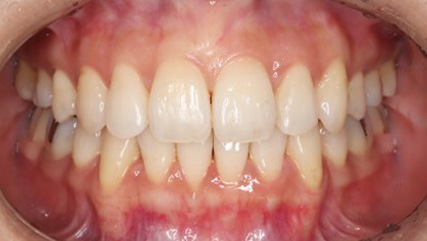

治療前

治療終了前

でこぼこがある状態になります。乱ぐい歯とも言われます。見た目がよくない審美障害が主な問題点ですが、その他にもでこぼこが多いことで、歯ブラシによる清掃性が悪くなり、結果、虫歯や歯周病のリスクも上がってしまいます。治療期間が短く済むことも多い為、気になった段階で早期に相談された方が良いと思います。